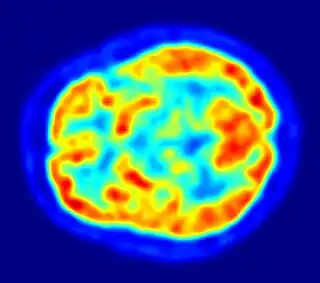

La medicina nuclear es una especialidad de la medicina en la que se utilizan radiotrazadores o radiofármacos (formados por un fármaco transportador y un isótopo radiactivo) para el diagnóstico y tratamiento de enfermedades. Estos radiofármacos se aplican dentro del organismo humano por diversas vías (la más utilizada es la vía intravenosa).

Imagen de resonancia magnética nuclear de una cabeza humana

PET tomado con un ECAT Exactitud HR+